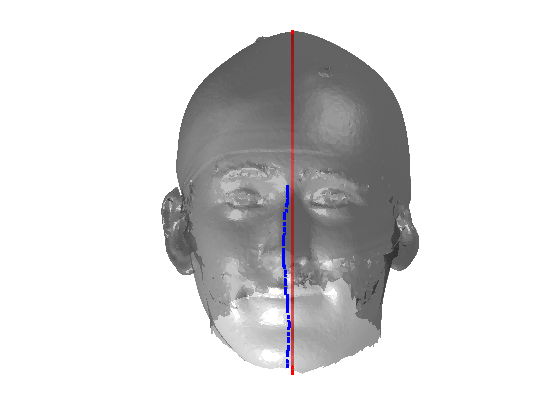

Fig. 9 shows examples of the fitted model (trained on FRGC data) on the first four subjects in our Headspace training set. Note that the mean of the landmarks in the sparse model is centred on the orgin, and so the scan data is moved towards that and becomes frontal in pose. We note that other researchers [28] have used 3D landmark localisation to find the head, but often this only includes landmarks that are relatively easy to localise, namely inner eye corners and nose. Localising more landmarks over a wider facial area has a number of advantage in terms of cropping, pose normalisation and global 3D template warping, all of which are described later.

|

|

|

|